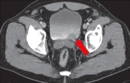

Mesanede İdrar Kalmasının NedenleriMesanede idrar kalması, tıpta "rezidüel idrar" olarak adlandırılan bir durumdur ve bu, mesanenin tam olarak boşalamadığı anlamına gelir. Bu durum, birçok sağlık sorununun belirtisi olabileceği gibi, idrar yolu enfeksiyonlarından nörolojik hastalıklara kadar geniş bir yelpazede sebeplerle ilişkili olabilir. Aşağıda, mesanede idrar kalmasının başlıca nedenleri ele alınacaktır. 1. Anatomik SorunlarAnatomik yapısal bozukluklar, mesanenin normal işlevini etkileyerek idrar kalmasına yol açabilir. Bu bozukluklar arasında:

İdrar sonrası mesanede idrar kalması hissi, çeşitli sağlık sorunlarının bir belirtisi olabilir. Bu durumun altında yatan bazı olası nedenler şunlardır: mesane kaslarının zayıflığı, idrar yolu enfeksiyonları, prostat problemleri (erkeklerde), mesane taşları veya tümörleri gibi yapısal sorunlar, sinir sistemi ile ilgili problemler veya bazı ilaçların yan etkileri.

Olası Nedenler arasında prostat büyümesi, mesane enfeksiyonları, sinir hasarı veya mesane taşları yer alabilir. Bu tür sorunlar, idrar akışını engelleyebilir ve mesanenin tam olarak boşalmasını zorlaştırabilir.